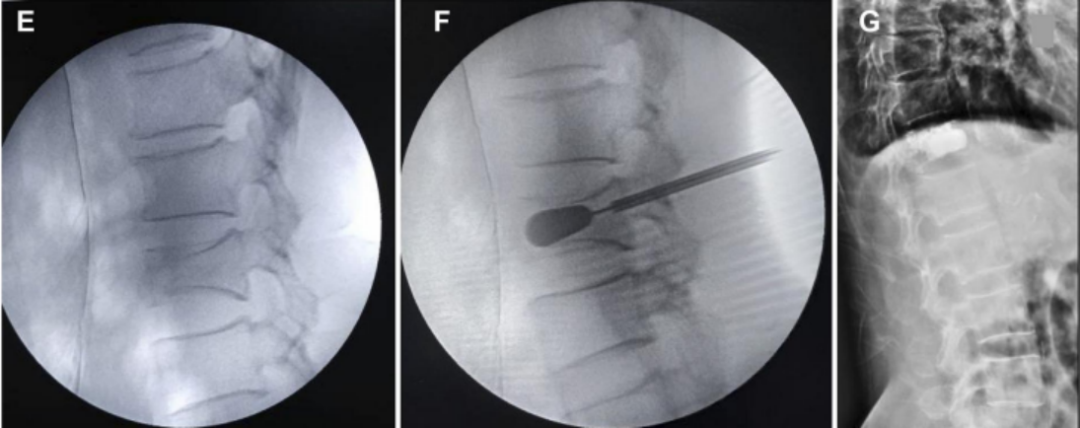

椎体成形术(PVP):

经皮椎体成形术(percutaneous vertebroplasty,PVP)是经皮由椎弓根置入,骨水泥注入椎体,从力学上增强其结构强度。

椎体成形术(PVP)病例

经皮球囊扩张椎体后凸成形术(PKP)

①正位、侧位影像监测下,经皮由椎弓根置入;

②置入导管球囊扩张,向气囊内充气扩张,以恢复椎体高度;

③放出气囊内气体,移走气囊,注入骨水泥维持矫正后形态

经皮球囊扩张椎体后凸成形术(PKP)病例